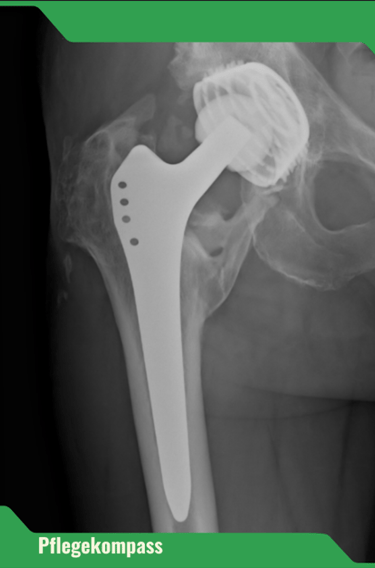

Ein Sturz bedeutet weit mehr als nur ein Ausrutschen – die Folgen reichen von Knochenbrüchen bis zum Verlust der Selbstständigkeit. Besonders häufig betroffen: der Oberschenkelhalsbruch. Über 90 % dieser Brüche entstehen durch Stürze.

Nach einem solchen Ereignis sinkt die Mobilität deutlich, und viele Betroffene können nicht mehr in ihrem gewohnten Zuhause bleiben. Deshalb ist Sturzprävention ein zentraler Bestandteil professioneller und häuslicher Pflege.

Nur 40–60 % der Betroffenen mit Hüftfraktur erreichen ihre vorherige Mobilität wieder.

Rund 10–20 % werden danach dauerhaft in Pflegeeinrichtungen aufgenommen.

Innerhalb von 6 Monaten nach einer Hüftfraktur versterben 57,8 % der Männer und 32,9 % der Frauen in Pflegeeinrichtungen.